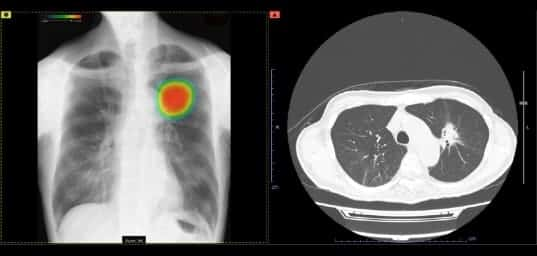

胸部X線画像におけるCXR-AID

AIを用いた胸部X線画像の判定では、撮影した胸部単純X線画像をAIにて自動解析し、結節・腫瘤影(がんなど)、浸潤影(肺炎など)、気胸が疑われる領域を検出しマーキングします。結節影の有無を今までよりも正確に判断することが可能になり、その領域を医師が再確認することで、見落し防止を支援することが可能となります。

病変の早期発見につながったり、病変の見落としが減ったりすることで、より安心できる医療が提供できると考えます。

当院で胸部X線を撮影した方は全員、医師の確認に加えてAIでも確認しています。